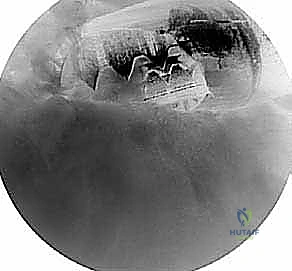

الخطوة الأولى: استكشاف المفصل (Diagnostic Arthroscopy)

يتم إدخال كاميرا المنظار (Arthroscope) عالية الدقة (يستخدم د. هطيف تقنية 4K) من خلال ثقب خلفي صغير. يتم فحص المفصل الحقاني العضدي (Glenohumeral joint) بالكامل للتأكد من عدم وجود إصابات أخرى مرافقة، مثل تمزقات شفا المفصل (SLAP tears) أو التهاب وتر ذات الرأسين.

الخطوة الثالثة: تجميل الأخرم وتوسيع المساحة (Acromioplasty)

هذه هي الخطوة المحورية. بمجرد كشف العظم، يتم تقييم النتوءات العظمية (Spurs) وشكل الأخرم المعقوف. باستخدام أداة كشط عظمية دوارة دقيقة (Burr)، يقوم الجراح بنحت السطح السفلي لعظم الأخرم، وإزالة النتوءات العظمية، وتحويل الأخرم من الشكل المعقوف (النوع 3) إلى الشكل المسطح (النوع 1).

يتم أيضاً تحرير أو قطع جزء من الرباط الغرابي الأخرمي (CA ligament) إذا كان متصلباً ويساهم في الضغط. النتيجة النهائية هي مساحة واسعة ومسطحة تسمح لأوتار الكتف بالانزلاق بحرية تامة دون أي احتكاك.